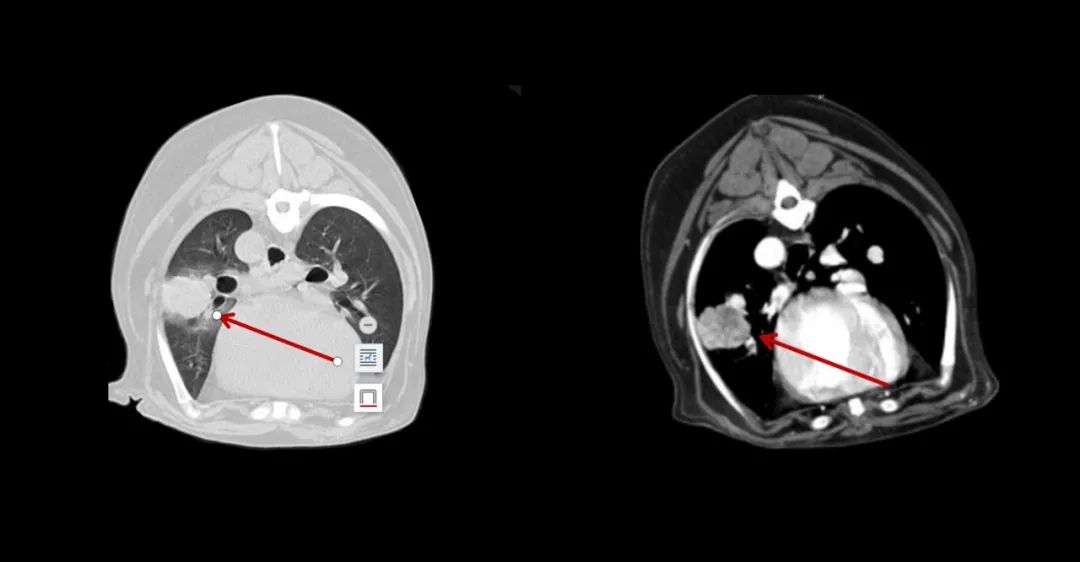

▲7歲成年犬,乳腺癌術后1年,發(fā)現肺部轉移。

640 (3).jpg